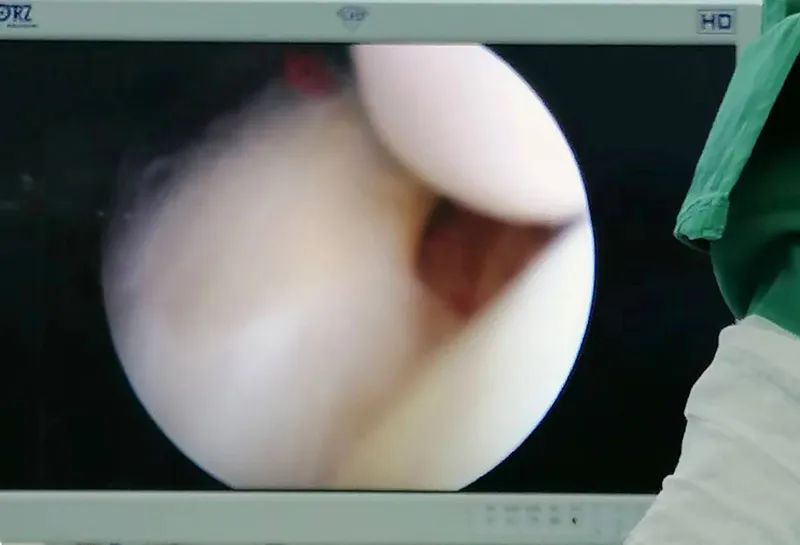

決定行

“肩關(guān)節(jié)鏡下肩袖損傷修補(bǔ)術(shù)”

這種微創(chuàng)手術(shù)是通過4-5mm通道進(jìn)鏡,在鏡下能直視觀察肩關(guān)節(jié)內(nèi)部及肩峰下的一些病變,并可直接在鏡下進(jìn)行手術(shù)或指導(dǎo)切開手術(shù)方法的選擇。保持肩關(guān)節(jié)原有的解剖生理結(jié)構(gòu),損傷小,恢復(fù)快,并發(fā)癥少。是用于檢查、診斷和治療各種關(guān)節(jié)疾病的一種新型手段。